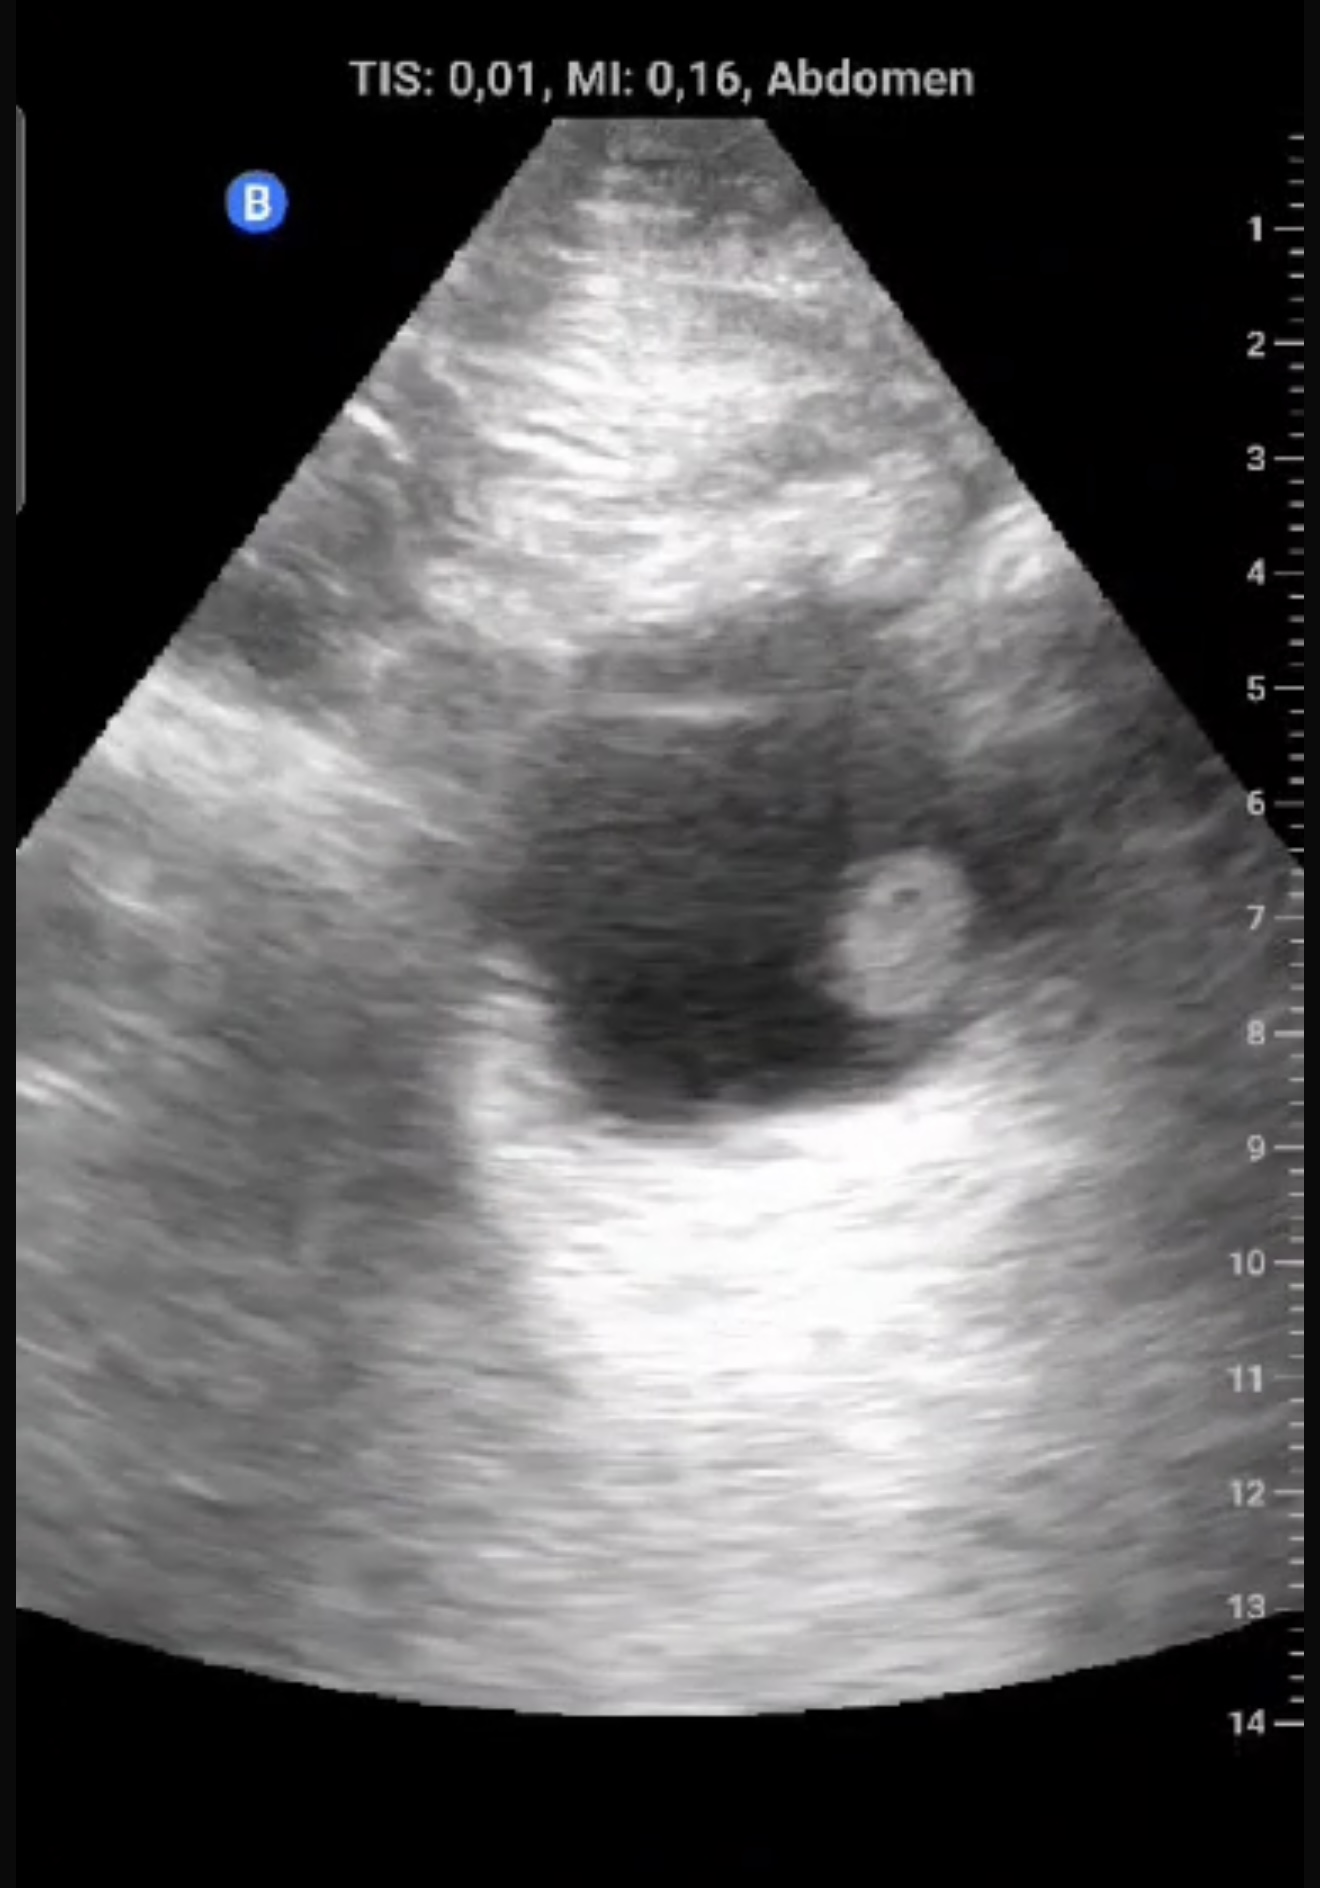

Exfumador, HTA, hipercolesterolemia, cirrosis hepática por alcohol. Hombre de 58 años que refiere episodio de hematuria macroscópica hace dos semanas, coincidiendo con un esfuerzo físico intenso el día previo. No presenta disuria, fiebre, poliaquiuria, ni dolor. En controles posteriores, no había recurrencia de hematuria y el paciente se encontraba asintomático.Exploración física sin hallazgos relevantes. Ecografía realizada en consulta en apenas 5 minutos mostró una masa en la cara lateral izquierda de la vejiga, de 1,5 x 1,3 cm, con características sugerentes de lesión tumoral superficial.

Descripción de los hallazgos ecográficos y las imágenes más relevantes para la resolución del caso

Lesión sólida, pediculada, de bordes definidos y fronda larga en la cara lateral izquierda de la vejiga.

Se sospechó un tumor vesical; pólipo vesical. Urología confirmó la lesión mediante cistoscopia, describiendo una masa papilar superficial de 2 cm en la pared lateral izquierda.